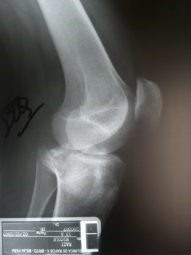

Fractura de plato tibial reducida bajo control artroscópico

Envíado por Dr. Luis Rodolfo Morales Choto